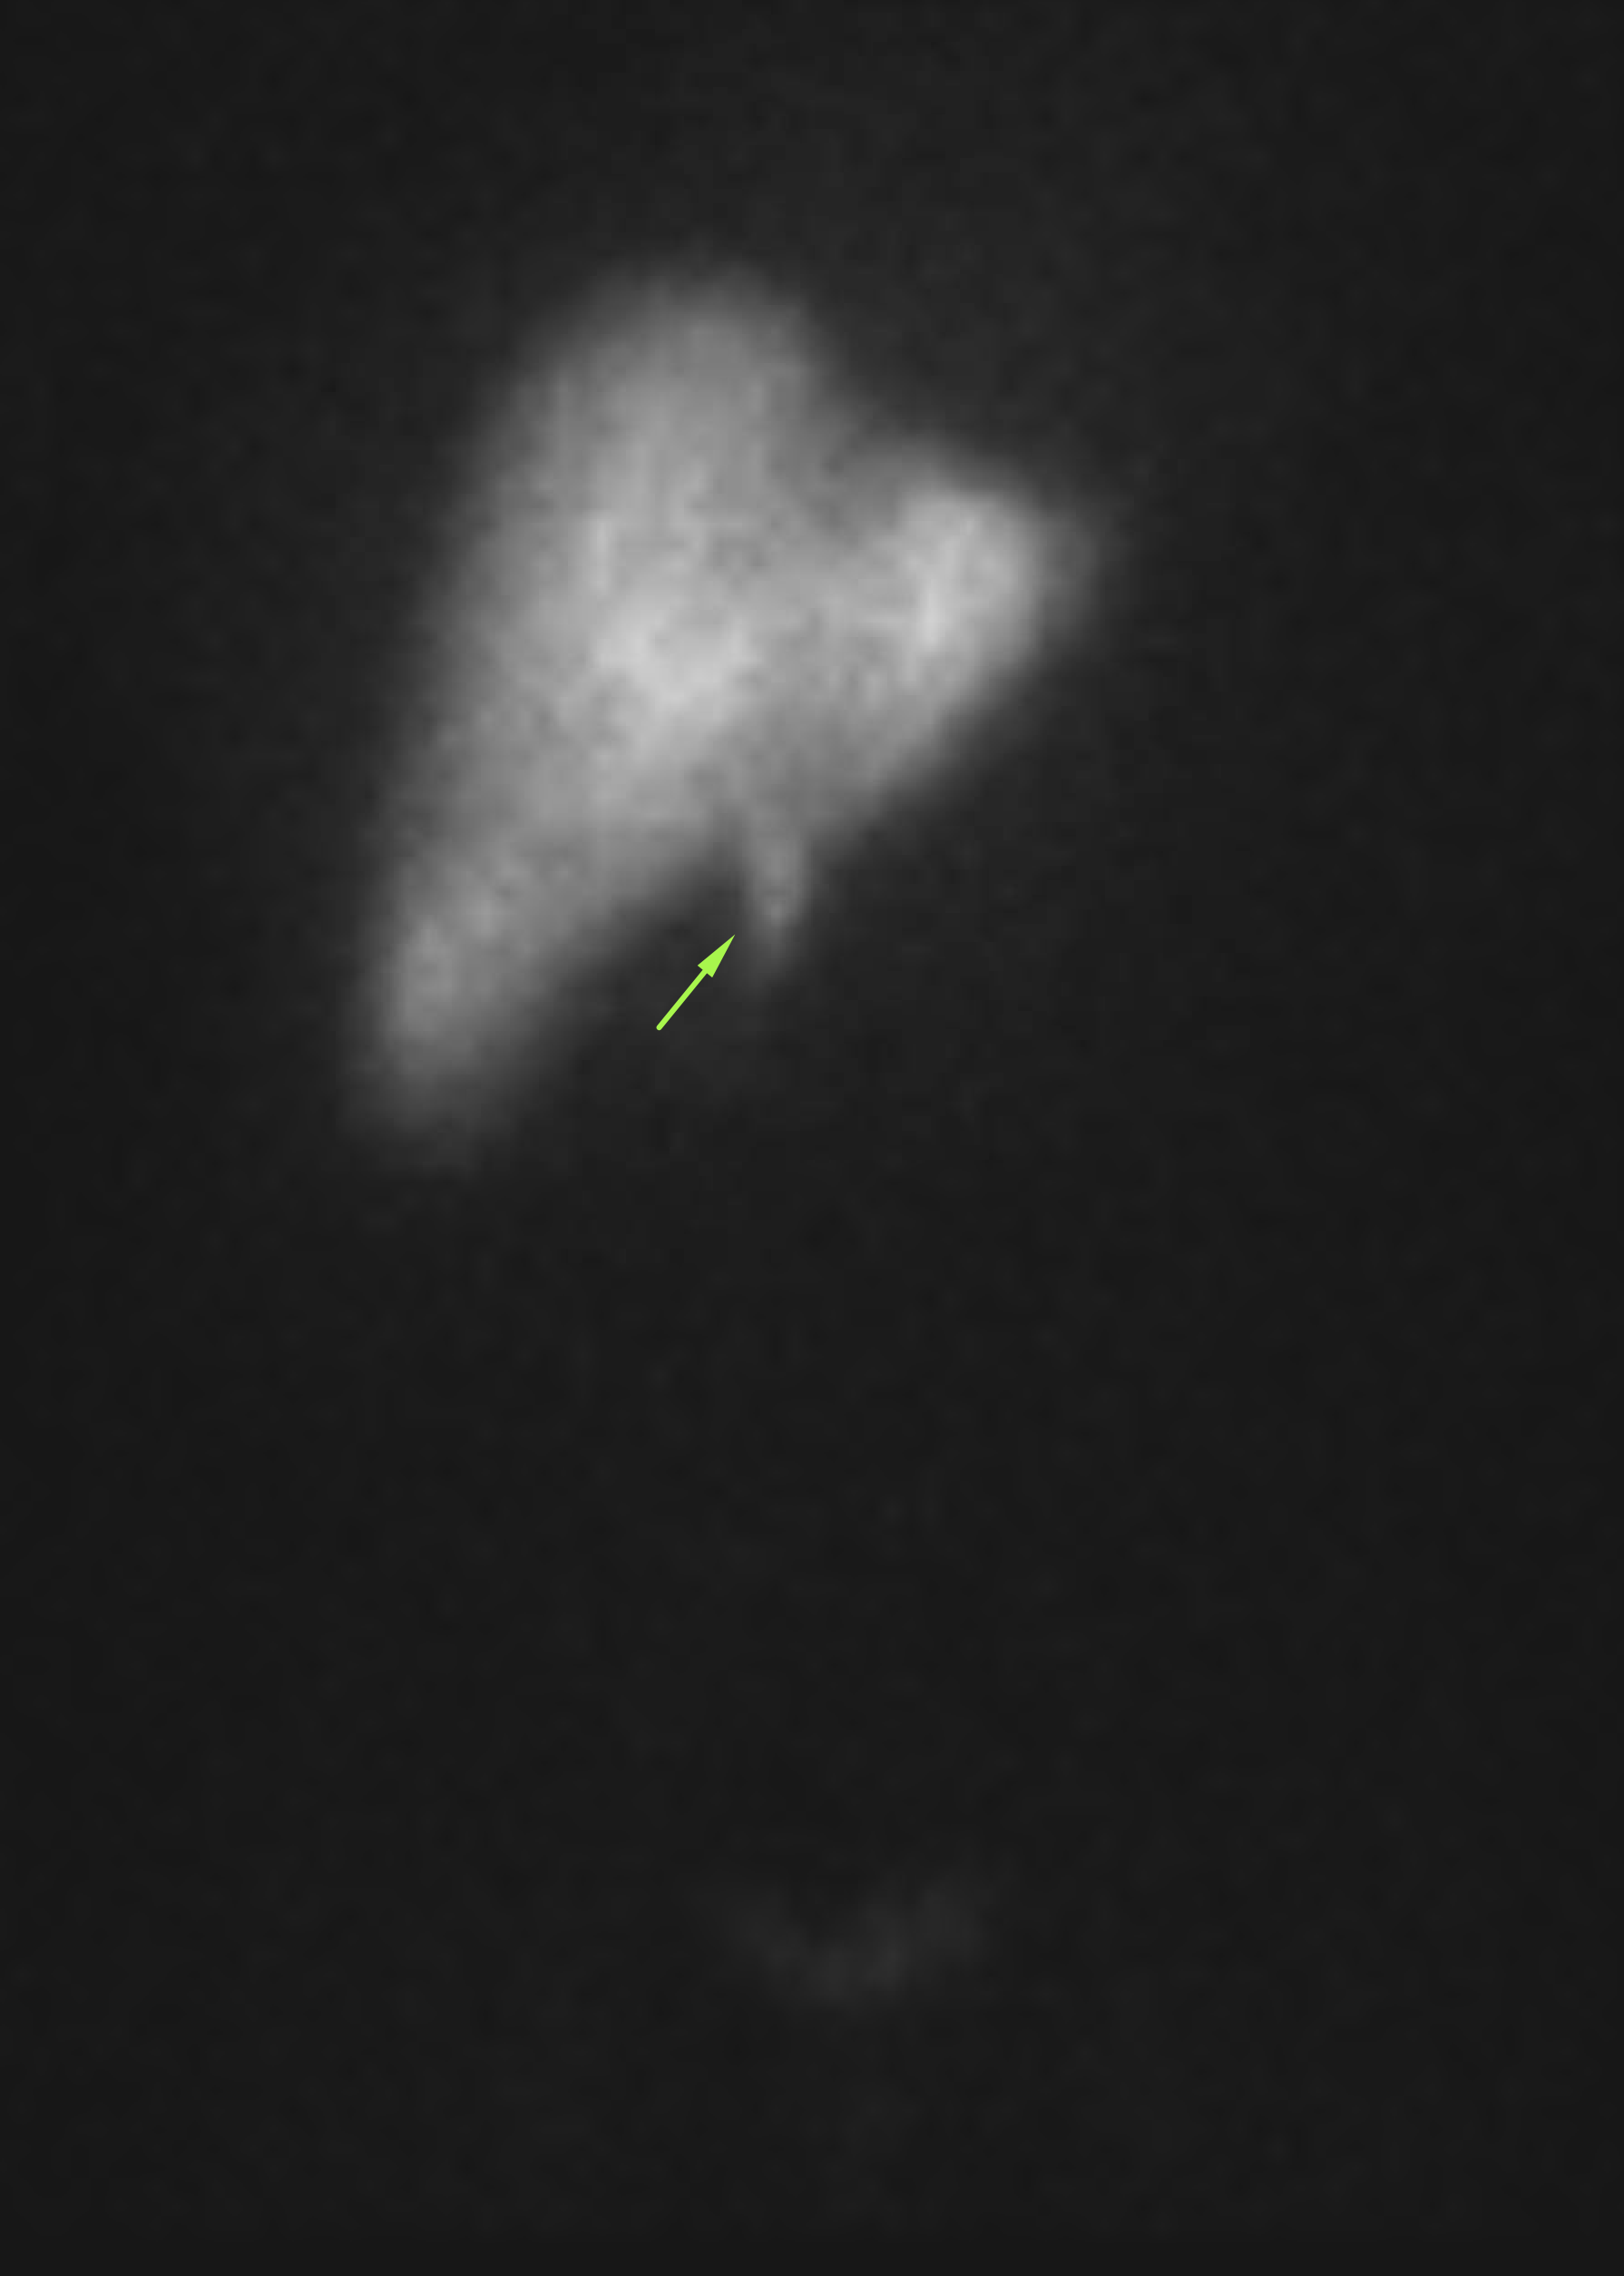

Age: 44

Sex: Male

Indication: Right upper quadrant pain

Radiotracer: Tc99m Mebrofenin

IV morphine administered at 1 hour

Sample ReportFindings consistent with acute cholecystitis.